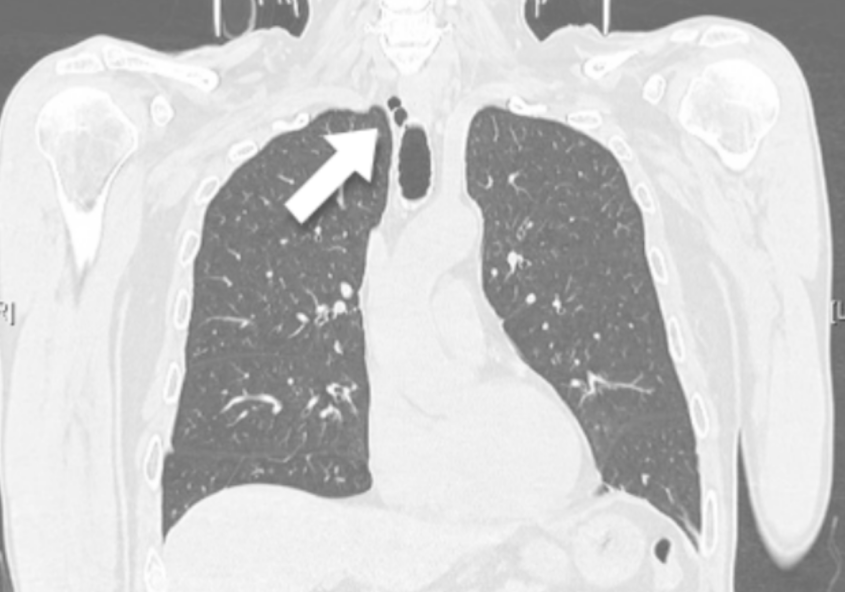

TERAPIA CON ANTI-ORMONI IN UN SUBDOLO CASO DI PNX CATAMENIALE

Lo pneumotorace (PNX) catameniale, l’espressione patologica più frequente dell’endometriosi toracica, è la patologia affrontata in questo articolo: attraverso l’analisi di un caso clinico, si giunge alla conclusione che la cura più indicata è la chirurgia con asportazione delle isole di endometriosi.